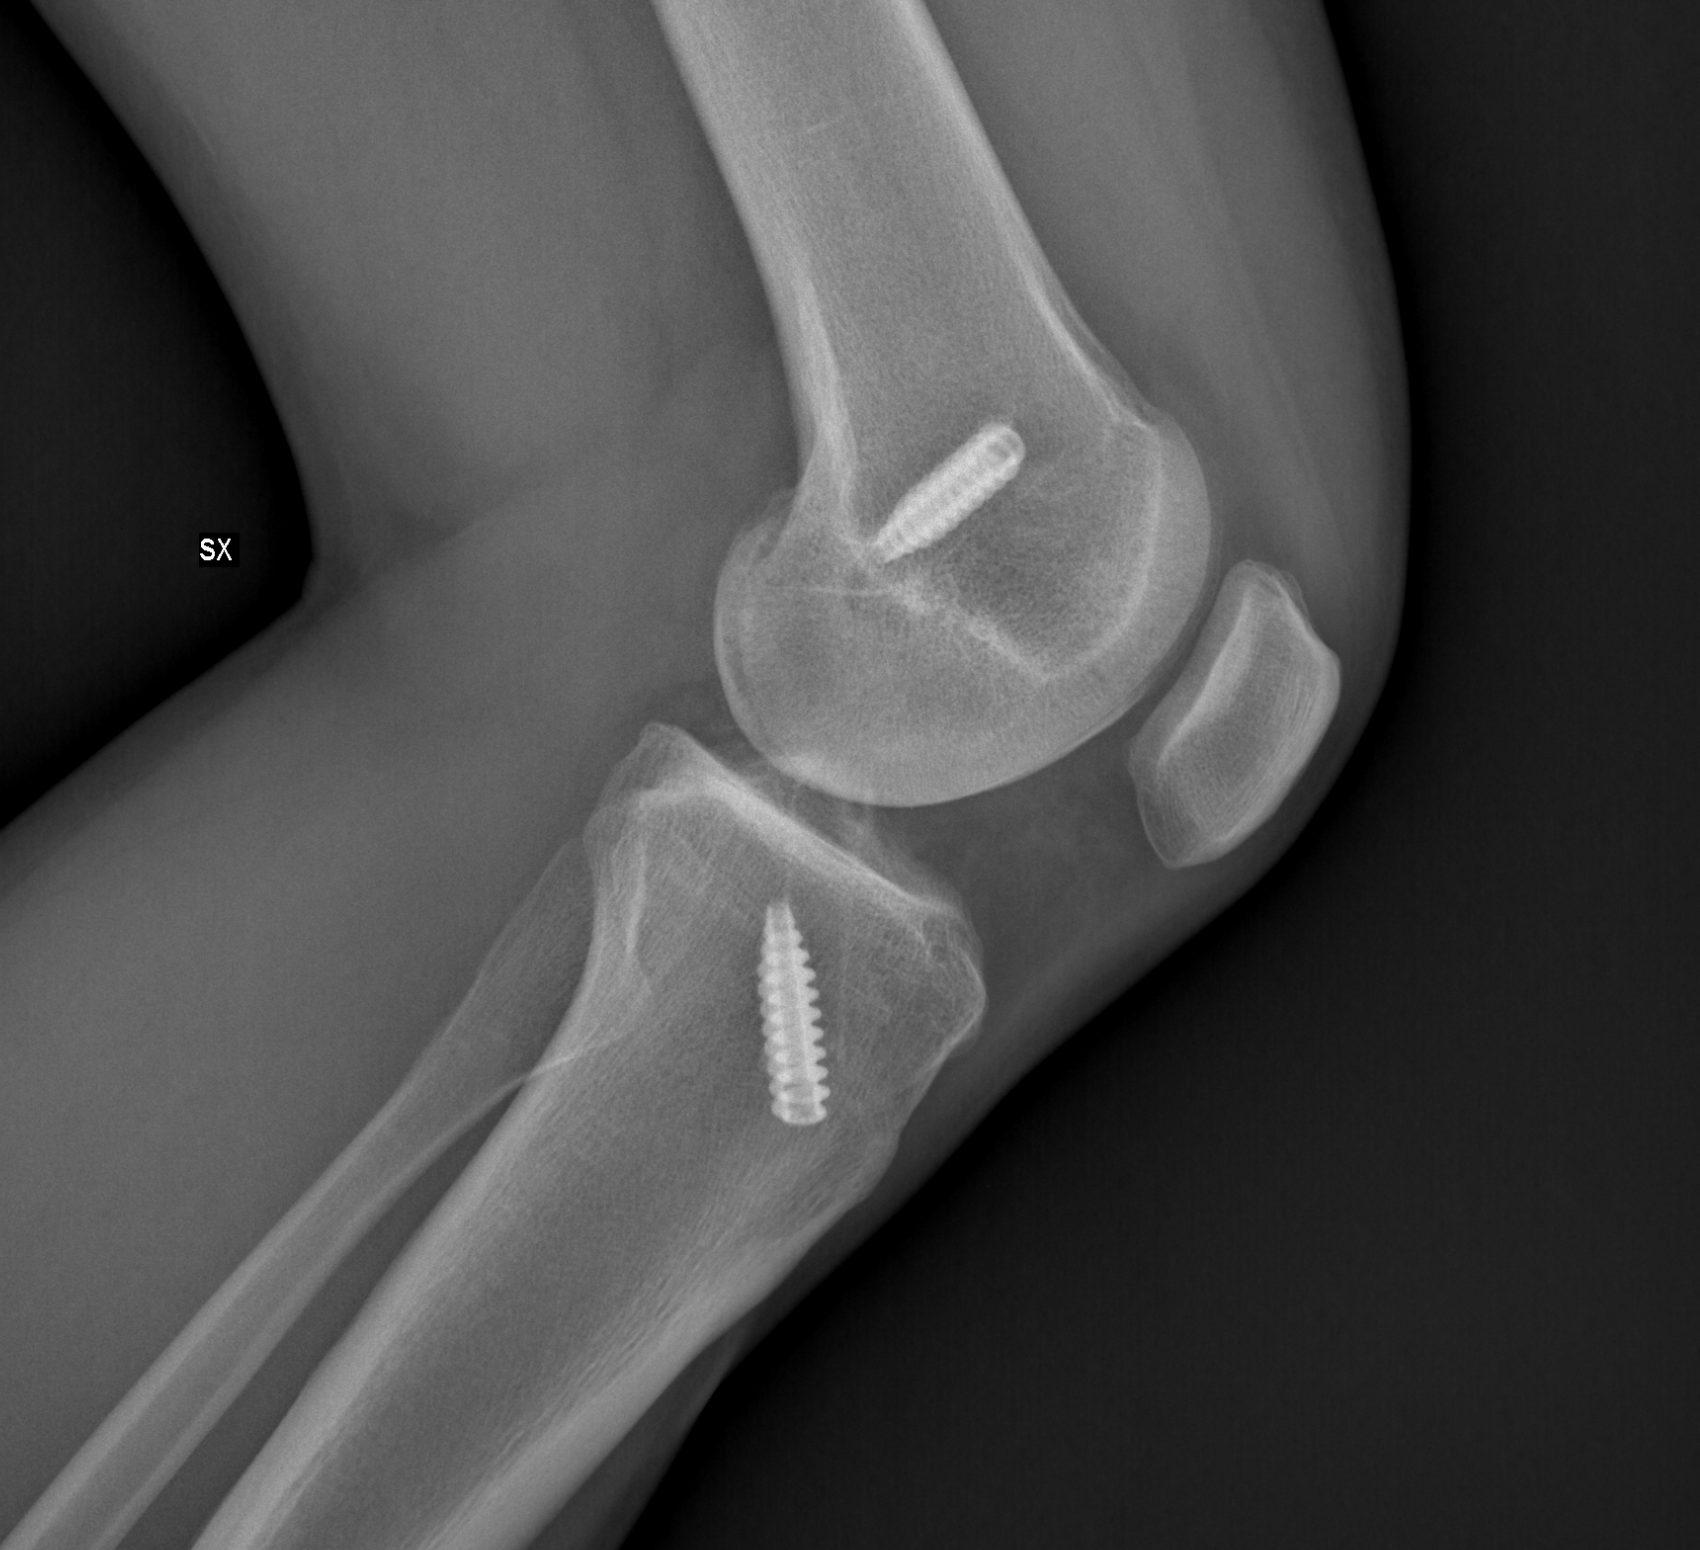

Risulta molto utile nella identificazione e nel monitoraggio delle fratture ossee, specie se presenti mezzi di sintesi metallici.

L’esame radiografico risulta indispensabile per verificare il corretto posizionamento delle protesi articolari (di spalla, di anca, di ginocchio, di gomito) e per monitorare nel tempo la loro condizione.